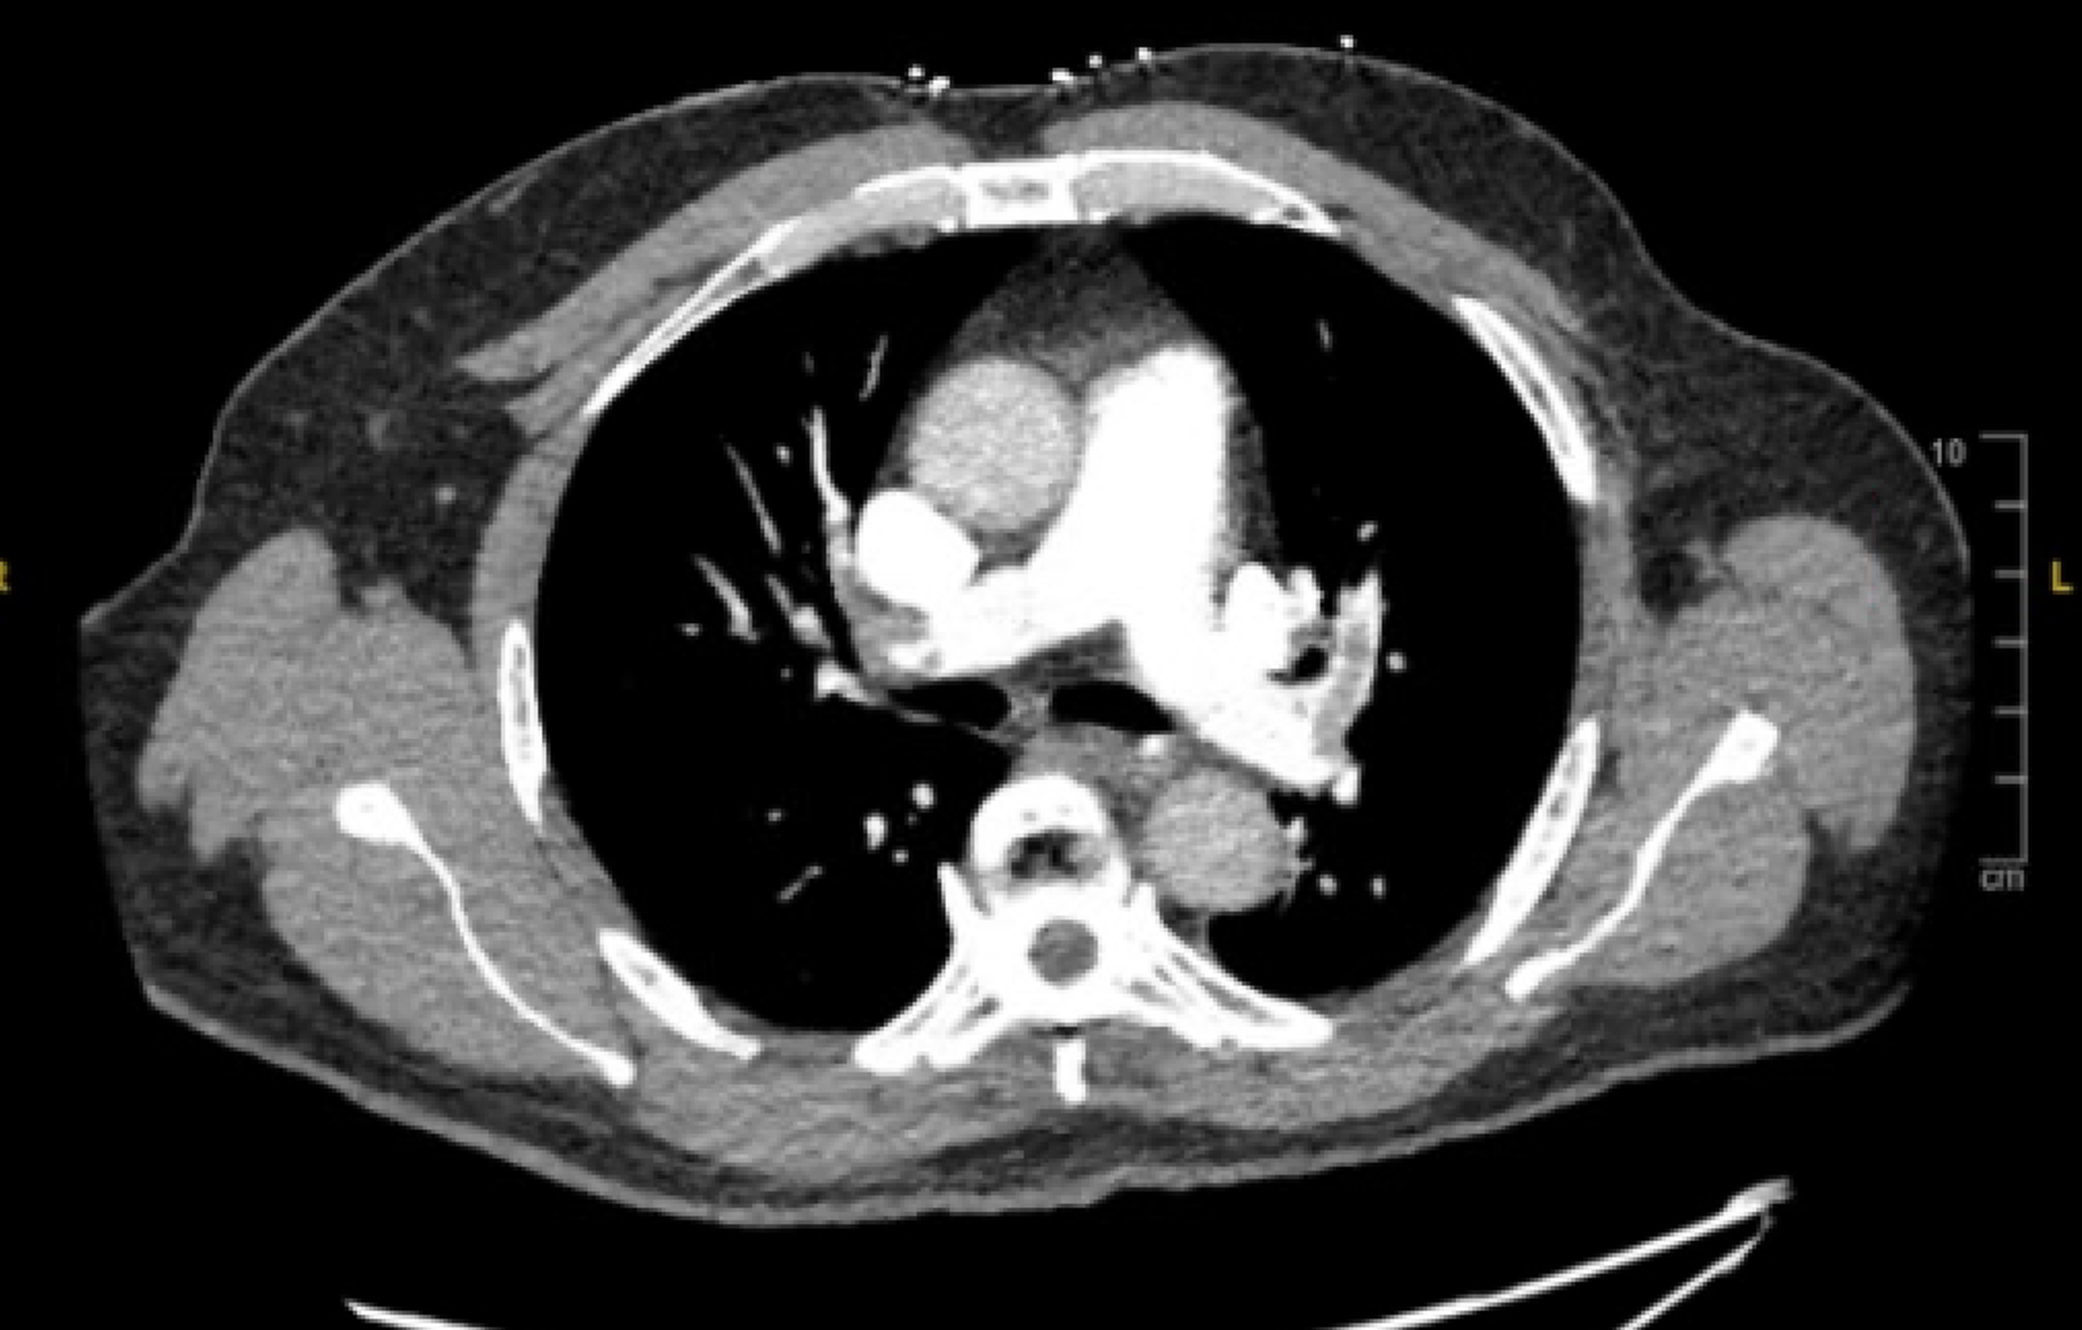

CT PE showing filling defects in the right and left pulmonary veins

Imaging Options: The first line imaging study is a CT pulmonary angiogram (CTPE/CTPA). Ventilation-perfusion (V/Q) SPECT is a second-line test, often used when contrast exposure is undesirable, such as in patients with significant renal dysfunction, or who have contraindications to radiation such as in pregnancy. The performance of ventilation perfusion SPECT scans for PE diagnosis is not well established2 and the result often ends up being “intermediate risk” for PE, which can complicate decision making.